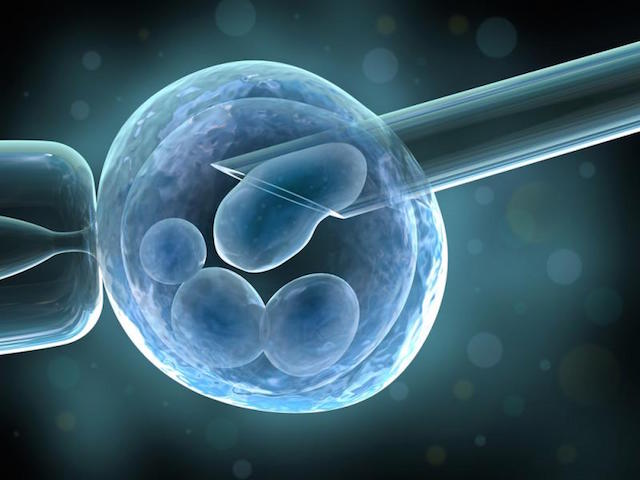

Това е процес, при който яйцеклетка е отделена от яйчника на майката, оплодена със сперматозоиди на бащата в лабораторни условия и върната в матката на майката.

“Щом веднъж Стептоу и Едуардс успяват да оплодят яйцеклетка, те много бързо разбират, че трябва да ограничат броя получени ембриони за трансфер, за да намалят вероятността за многоплодна бременност”, обяснява Макнами. “Развитието на крио технологиите през 80те години довело до трансфер само на 1-2 ембриона и замразяването на останалите за бъдеща употреба. По този начин се спестява повторно извличане на яйцеклетки.”

Замразяване на ембриони за последващ трансфер

Техниката за директно инжектиране на сперматозоид в яйцеклетката, разработена в края на 80те, е пробив в лечението на мъжкия стерилитет.

Интрацитоплазмена спермална инжекция (ИКСИ)